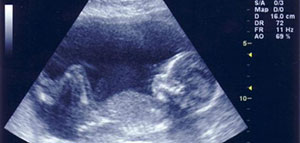

نسبة التحليل الرقمي للحمل الضعيف